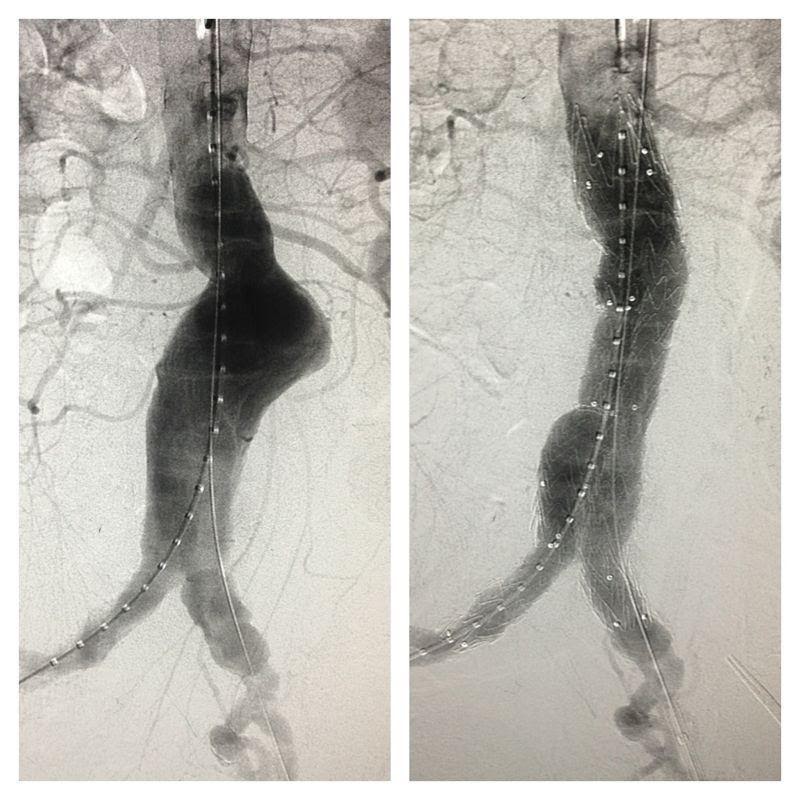

Modern diagnostic tools like ultrasonography (Figure 1) and computed tomography (CT) scan (Figure 2) makes the diagnosis much easier. The reported prevalence is around 4-8% in male and 1-2% in female after 70 year old. With ages beyond 80, the male to female ratio almost became 1:1.

Figure 1. Ultrasonographic picture of AAA